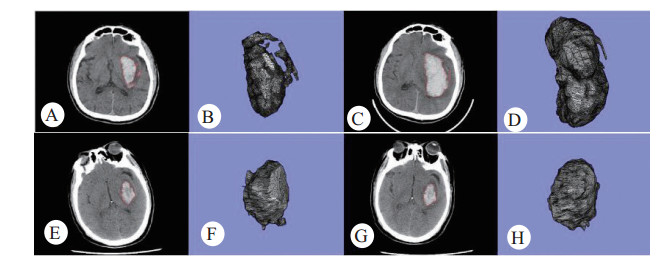

血肿空间形态:经mimics软件表面重建后可显示血肿空间形态,与断层平面形状相比明显丰富了感观信息:扩大血肿的初诊CT断层轮廓,主体仍大致呈椭圆形,但可见小突起及卫星状出血灶(图 1A),然而它的空间形态更明显、直观的反映出形态的不规则,表面存在较多突起,分枝,TQOT/mm2>1.95个/mm2(图 1B);复查后CT断层的血肿轮廓可见血肿面积扩大(图 1C);经过FEA计算,血肿体积增大>33%,其空间形态与初诊时相比,趋于规则和平滑,表面的突起、沟壑趋于消失,TQOT/mm2<1.95个/mm2,较初诊值减小(图 1D)。

| A:初诊扩大性血肿CT断层上的边缘轮廓形状;B:初诊扩大性血肿的空间形态;C:复查扩大性血肿CT断层的边缘轮廓形状;D:复查扩大性血肿的空间形态。E:初诊非扩大性血肿CT断层上的边缘轮廓形状;F:初诊非扩大性血肿的空间形态;G:复查非扩大性血肿CT断层的边缘轮廓形状;H:复查非扩大性血肿的空间形态。 图 1 扩大与非扩大血肿的CT与FEA三维重建形态比较 Fig 1 the comparison HE and not-HE morphology of CT and FEA 3D reconstruction |

另一例非扩大血肿的初诊CT断层:血肿轮廓大致呈椭圆形,边缘较规则(图 1E),初诊血肿空间形态也相对规则和光滑,TQOT/mm2<1.95个/mm2(图 1F)。复查CT断层的血肿轮廓:面积没有发生显著扩大,轮廓形状与初诊时相比并无明显改变(图 1G);复查血肿空间形态与初诊相比,体积未发生扩大,但边缘更为平滑呈趋于球状,TQOT/mm2较初诊值减小(图 1H)。

总之,非扩大性血肿表面形态与扩大性血肿相比,表面相对规则,结构相对简单,大致倾向于类球形。扩大性血肿表面形态复杂,不规则,表面存在分枝状突起、沟壑、卫星小血肿等,但随着时间的推移,这些表面结构趋于消失,HE与非HE血肿的表面形态均存在趋于球形变化的趋势。